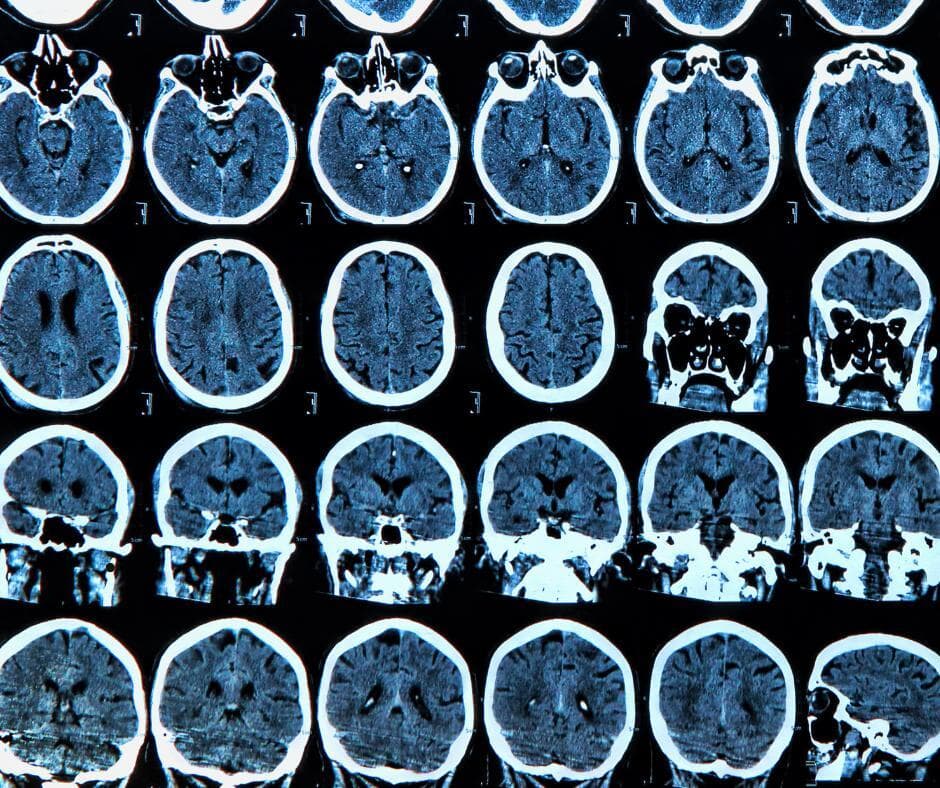

In addition to its culinary use, cinnamon may promote longevity and cognitive health through anti-inflammatory, anticancer, and immunomodulatory properties. A unique compound in cinnamon, cinnamaldehyde, is linked to the inhibition of amyloid-beta plaque buildup in the brain (a tell-tale sign of Alzheimer’s).

Notably, one in-vivo study identified that methanol extract from cinnamon bark may inhibit amyloid-beta production, thus aiding in the prevention of Alzheimer’s disease.

As the study progressed, researchers investigated distinct cinnamon components such as eugenol, cinnamic acid, and cinnamaldehyde. These analyses revealed cognitive protective effects, including the inhibition of amyloid plaques, anti-inflammatory properties, and anti-cell death mechanisms.